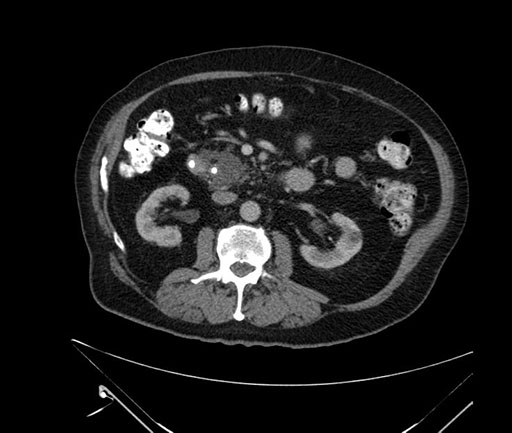

Whipple (pancreaticoduodenectomy) [case 7]

Axial - stented